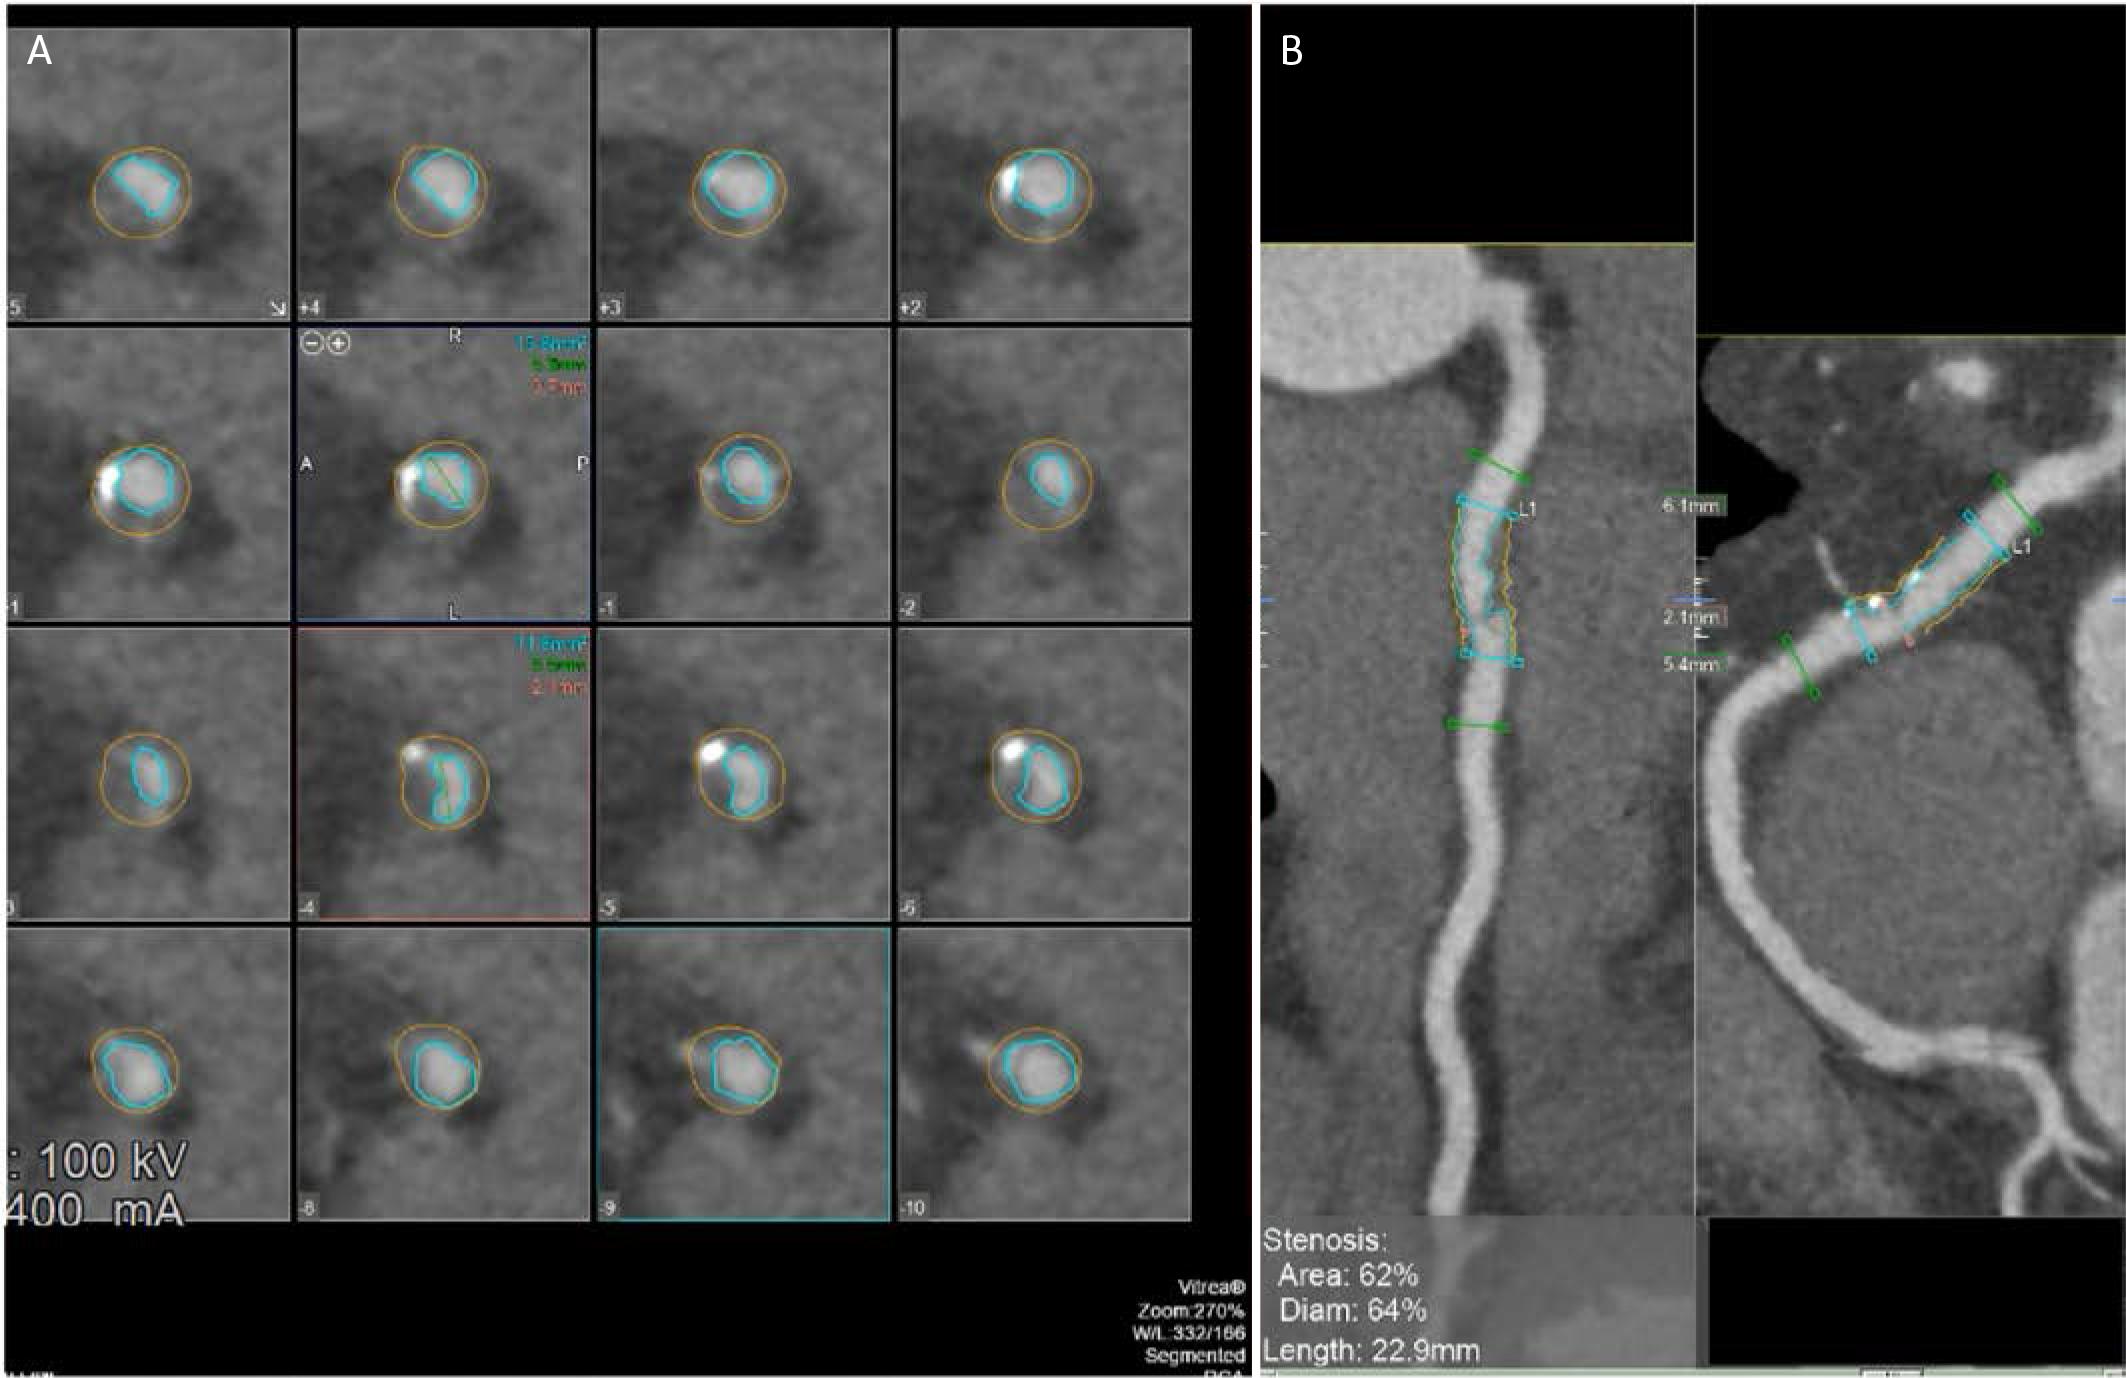

Artificial intelligence (AI)-enhanced risk stratification in CAD has expanded rapidly, with many models trained and validated in stable or suspected stable CAD cohorts, often leveraging CCTA-derived plaque and stenosis quantification and providing incremental prognostic value for future events (Figure 2).56 In contrast, NSTEMI-specific AI tools remain comparatively underdeveloped. Although machine-learning-based scores for ACS exist (GRACE 3.0 for NSTE-ACS risk assessment), much of the supporting evidence comes from retrospective/registry datasets and external validation rather than models trained and tested within contemporary, unselected troponin-positive NSTEMI pathways.57 This limitation is clinically important because guideline-directed practice still relies on traditional risk scores (GRACE/TIMI) to guide early risk stratification and invasive timing decisions.11 A critical next step is prospective head-to-head validation in NSTEMI comparing AI models against GRACE/TIMI (discrimination, calibration, net reclassification), and, most importantly, testing whether AI-guided strategies can improve decisions and reduce events without delaying care in truly high-risk patients.

Automated coronary plaque quantification and stenosis assessment using CCTA post-processing software. A. Serial crosssectional images along the lesion, with automated luminal (inner contour) and vessel (outer contour) segmentation enabling precise assessment of plaque burden and vessel remodeling. B. Multiplanar reconstruction views of the affected coronary segment with software-derived measurements indicating a 62% area stenosis and 64% diameter stenosis over a lesion length of 22.9 mm, consistent with hemodynamically significant obstructive CAD as defined by contemporary CCTA criteria.

Automated plaque analysis from CCTA has matured sub - stantially. Multiple deep-learning pipelines can now segment coronary arteries and quantify stenosis and plaque burden/composition with good reproducibility and agreement against expert readers and invasive reference standards. A recent American consensus states that, among patients with visually evident plaque on CCTA, adding quantitative plaque analysis may be useful to enhance risk assessment and guide the intensity of preventive therapies.58 In the multicenter international CONFIRM2 registry, AI-guided quantitative CCTA driven mainly by noncalcified plaque burden and diameter stenosis improved 3-year MACE risk stratification compared with standard clinical CT metrics (including CAD-RADS, coronary calcium score, and the modified Duke Index), with higher discrimination and significant net reclassification.59